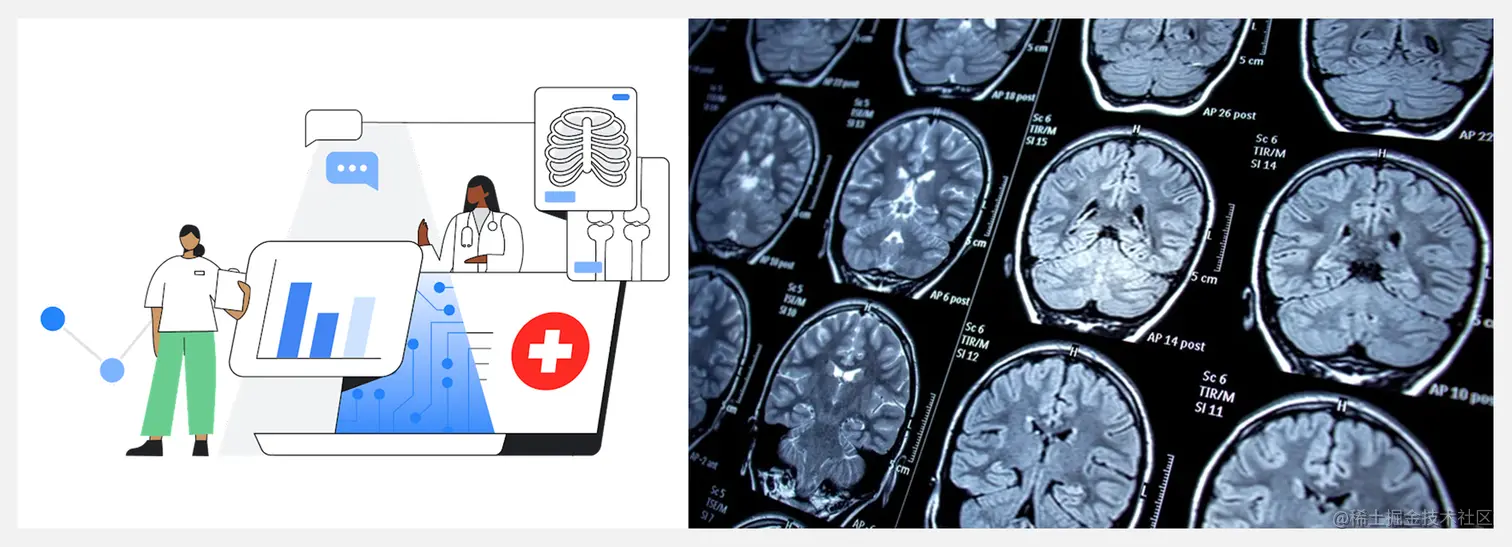

Google Cloud 近日推出了新的人工智能医学成像套件(Medical Imaging Suite),使用人工智能算法扫描医学图像,提供更快、更准确的诊断结果。这能缓解许多医院放射科医生和其他医护的巨大工作量,提高运转效率吧,同时也能改善医疗服务水平和患者的护理结果。

Medical Imaging Suite 的组件包括:Imaging Storage、Imaging Lab、Imaging Datasets & Dashboards、Imaging AI Pipelines。Google表示,医学成像套件旨在解决人工智能和机器学习模型开发时面临的常见痛点。

医学影像是医院用于诊断病人的最关键工具之一,每年有数十亿张图像被临床医生用来辅助诊断病因,占所有医疗数据的90%左右。视觉人工智能有望在医疗保健领域产生巨大的影响,而 Google 的医学影像套件展示了科技公司与医疗保健公司携手前进的可能性。